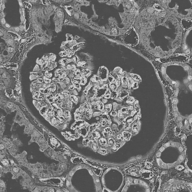

Image datasets in digital pathology applications often consist of consecutive slides stained differently, each staining providing specific information on the same region of interest (see Figure 1, first row). Even though differently stained slides appear very different, there is often a significant amount of consistent information between them. For example, they may both share the same counterstain (e.g. haematoxylin), or they may highlight different parts of the same structure.

The analysis and integration of information from different stainings is usually performed with reference to a specific organ, structure, or pattern observed in the tissue. For example, to diagnose pathologies such as breast cancer or kidney allograft rejection it is necessary to study the inflammatory micro-environment of the organ. In these cases, the relevant information is the distribution of immune cells (e.g. macrophages or lymphocytes) in relation to important structures of the organ, such as glomeruli for the kidney, or lobules for the breast.

To automatically perform such an analysis, the structure of interest (glomeruli, lobules, etc.) should be detected in each section irrespective of the individual staining modality. This is a typical application of deep learning, assuming that annotations for each staining are available. Thus, there is a high demand for annotations in digital pathology, currently limited by the availability of experts and the complexity of the required expert knowledge [5].

Objects to be segmented, e.g. glomeruli, are generally easily identified between stainings as globally they exhibit the same structure and texture, see Figure 1. It should therefore be possible to bias the network to learn stain invariant features. This work investigates this possibility by modifying the data presented to the network in an unsupervised manner. Borrowing domain adaptation terminology, herein the staining used for training and validation is referred to as as the source staining (irrespective of any transformations), and the stainings to which the network are applied as target stainings.